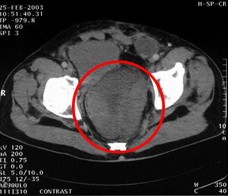

病例1 女,49歲。胃體癌晚期,胃竇增厚強(qiáng)化,與周圍粘連,腹膜增厚,腹腔廣泛轉(zhuǎn)移,伴大量腹水。放/化療失敗,無法手術(shù)。治療方案:腹腔灌注今又生2×1012VP/2次/周,共12周,同時灌注順鉑和5-氟尿嘧啶腹腔,后4…